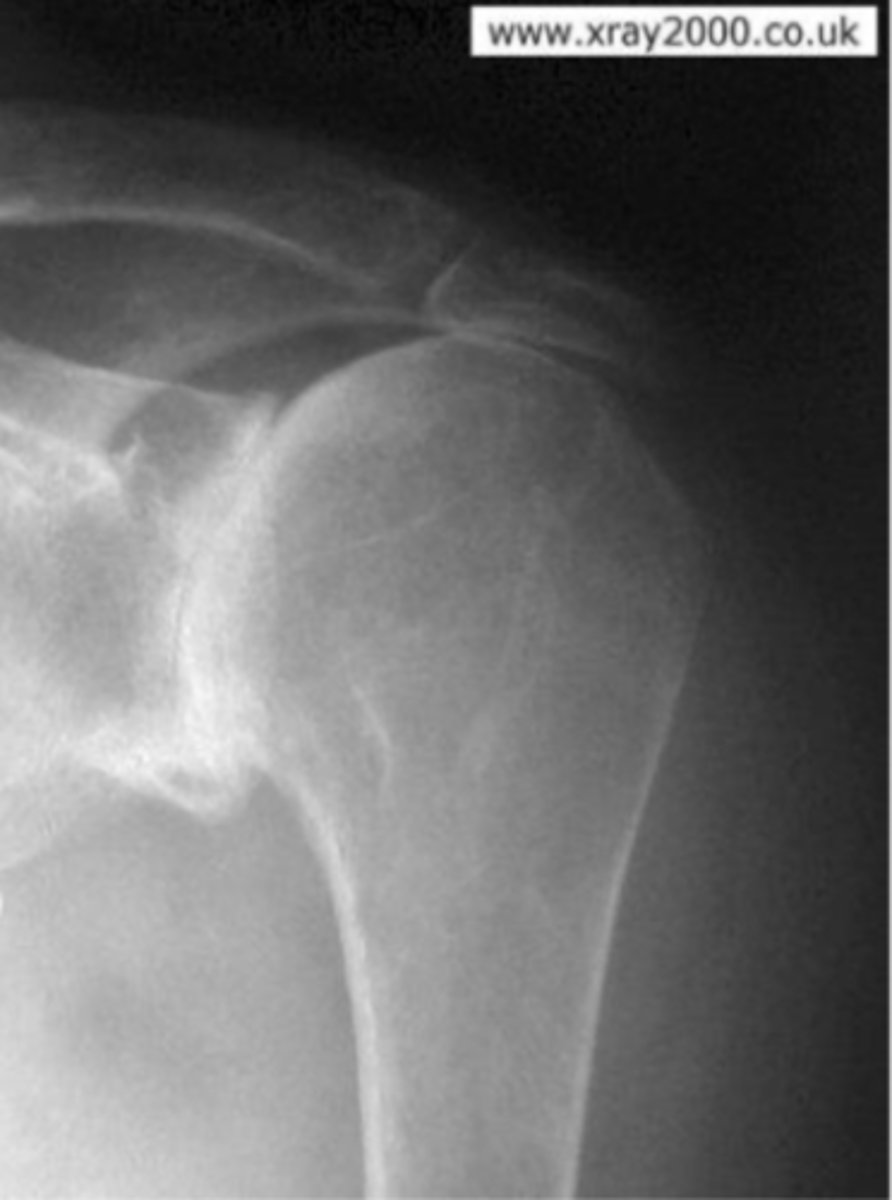

AP of the right shoulder

What view does this show?